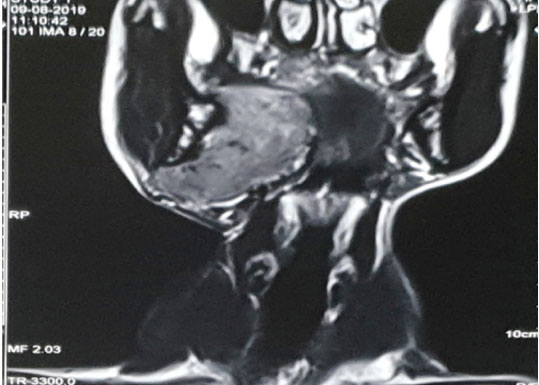

A 49-year-old male presented in our department with gradually progressive swelling in right cervical region for 8 years. The patient also complained of voice change for two months and decreased hearing in right ear for one month. Palpation revealed approximately 3 × 3.5 cm firm, non-tender, non-pulsatile, fixed swelling in right cervical region just below the angle of mandible. Oral cavity examination revealed firm, non-tender, non-pulsatile swelling medializing the right tonsil (Figure 1). Nasal endoscopy and laryngoscopy revealed a bulge in the nasopharynx and parapharyngeal space (Figure 2). Otoscopic examination demonstrated otitis media with effusion in right ear. There was no significant cervical lymphadenopathy. Cranial nerve examination was normal. Contrast enhanced magnetic resonance imaging (MRI) presented a 7 × 3.5 × 8 cm heterogeneously enhancing and circumscribed elongated soft tissue mass extending from submandibular area to parapharyngeal, tonsillar, and retromolar region with encasement of great vessels on right side (Figure 3).

Figure 3: Magnetic resonance imaging with gadolinium enhancement shows enhancing and circumscribed tumor in right parapharyngeal, tonsillar, and retromolar region. Coronal view.